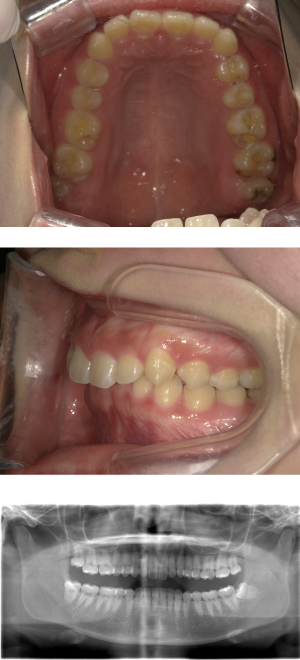

40代 女性 インプラント治療(右上64サイナス・GBR)

| 年代・性別 | 40代・女性 |

| 主訴 | 歯周病が進行し、抜歯適応となってしまったところにインプラント治療希望。 |

| 部位 | 右上⑥5④3② |

| 治療期間 | 約1年4ヶ月 |

| 費用 | ¥1,121,000(税込) |

| 副作用・リスク |

|